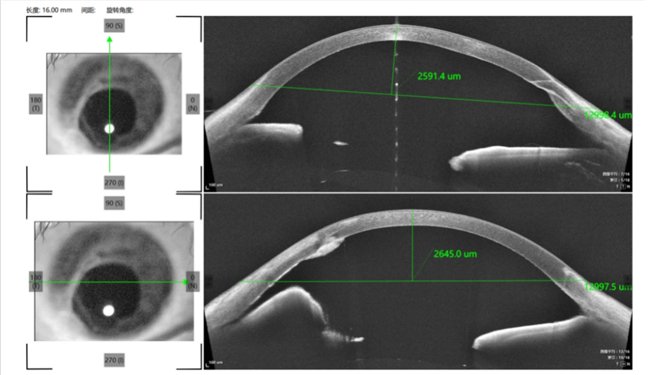

视光、斜视与小儿眼病科唐琰主任给嘟嘟做过检查后,表示可以为孩子验配巩膜镜。随后通过前节OCT、角膜地形图等检查,并结合嘟嘟角膜直径等情况,为嘟嘟确定了初始试戴片。

(前节OCT显示患者眼球破裂伤)戴上巩膜镜试戴片之后,嘟嘟觉得很好玩,“眼睛变成了绿色的,看起来特别有科技感(镜片评估时需要荧光素钠染色),镜片在眼睛里也不觉得难受,不会老想揉眼睛。”随后,医生通过各项评估发现,嘟嘟的矫正视力竟能恢复到1.0-!摘掉巩膜镜试戴镜片后,嘟嘟的眼睛也一切正常。